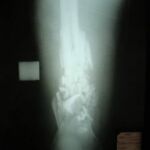

2.1. Учебная и клиническая база кафедры